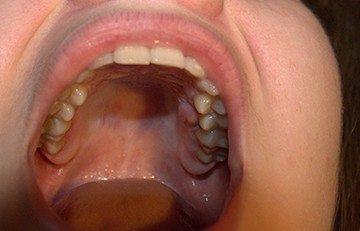

Пузырчатка

Слизистая оболочка, что находится в полости рта, иногда поражается пузырчаткой.

Образования имеют несколько форм, однако листовидная, вегетирующая и эритематозная дают о себе знать редко.

Возникает пузырчатка, если в работе иммунной системы происходит сбой и начинают вырабатываться антитела к клеткам, которыми образован слой эпидермиса. Они разрушаются, а в появившееся пространство попадает жидкость.

Пузыри, что возникают на слизистой рта, часто вскрываются при пережевывании пищи. Формируются эрозии, обладающие красным оттенком. На них присутствует белесый налет, который снимается довольно легко, но язвочки самостоятельно не заживают. Человек мучается от боли, изо рта исходит отвратительный запах.

Если в пузырьки попадает инфекция, жидкость в них мутнеет, выделяется гной. Пациент слабеет, присутствует субфебрильная температура. Начавшийся сепсис способен завершиться летальным исходом.